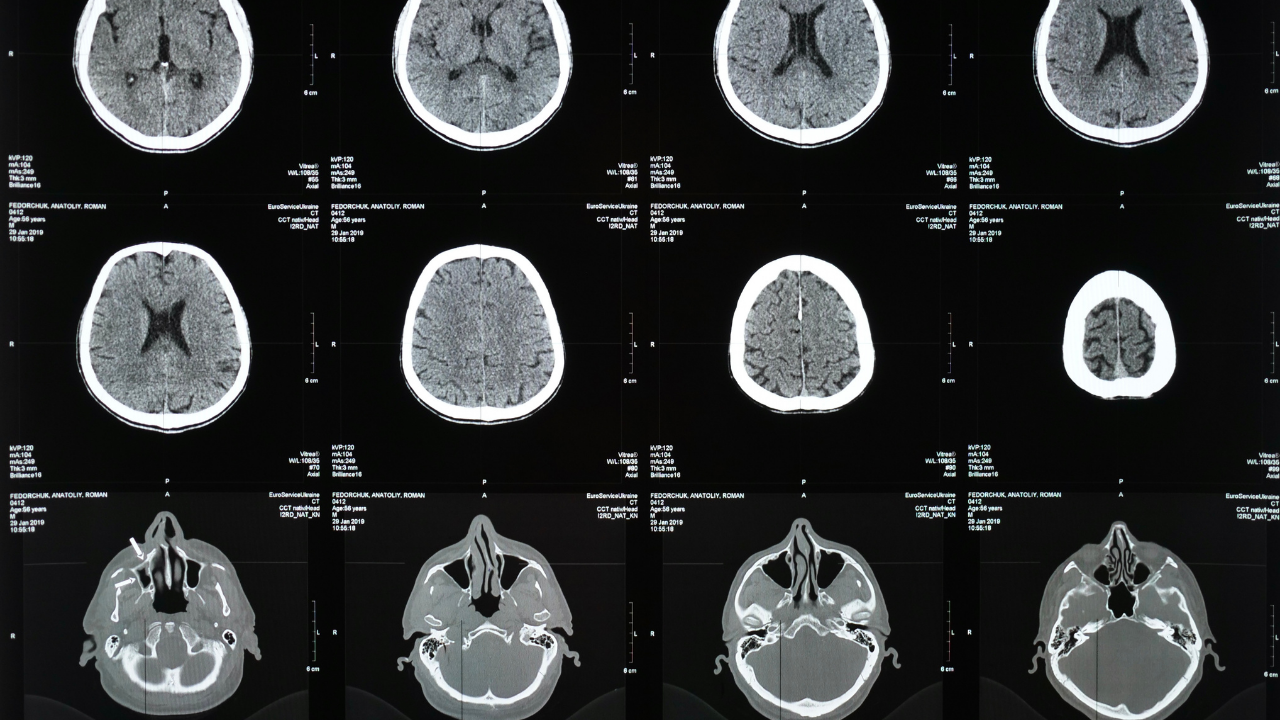

Uzmanlar, dünyada ve Türkiye’de inme (felç) sıklığının arttığını vurguluyor. Yaşlı nüfusta risk yükselirken; tansiyon, şeker, kalp hastalıkları ve sigara nedeniyle gençlerde de inme daha sık görülüyor. İnmenin önlenebilir bir hastalık olduğu, risk faktörlerinin kontrolünün hayati önemde olduğu belirtiliyor.